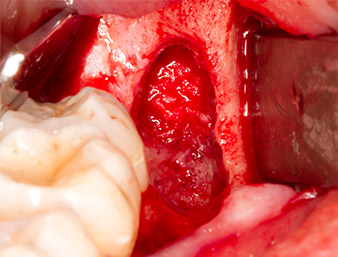

Using an instrument for periodontal debridement (Piezomed P1), the periodontal ligament space of the radix relicta was then widened minimally (Fig. 8).

The same activated instrument was inserted into the root canal and loosened the fragment as a result of its micro-oscillating vibrations (Fig. 9, 10).